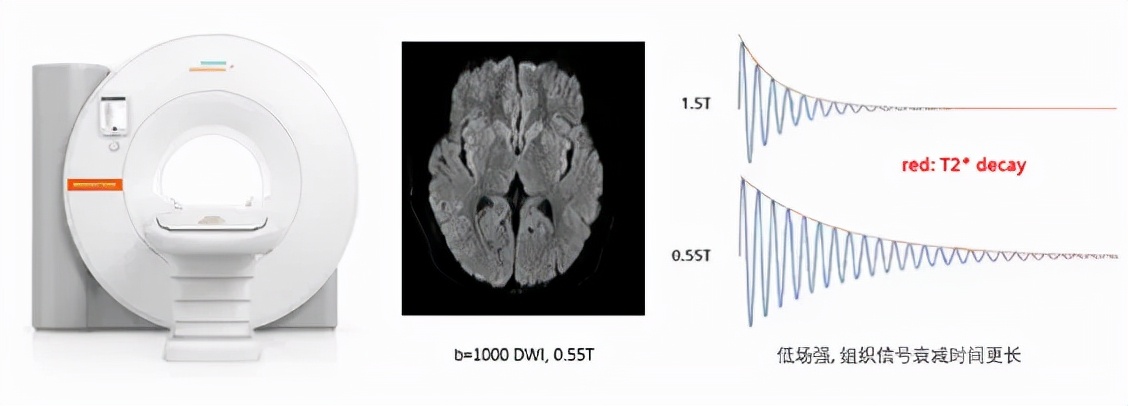

MAGNETOM Free.Max是全球首台采用高场磁共振设计结构(水平磁场)的0.55T超导磁共振,兼顾中等场强组织信号衰减时间更长和水平磁场高信噪比、高加速因子等优势,利用西门子医疗最新的成像和后处理技术,获得超出预期想象的临床图像质量和科研表现。